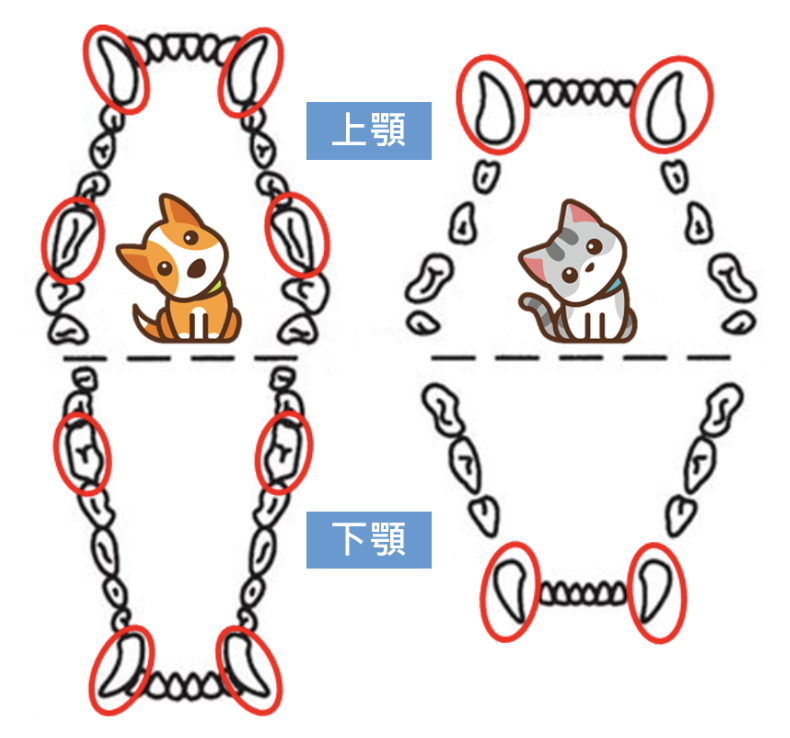

除了必須使用「牙科X光機」先確認毛孩寵物牙齒的狀況外,在犬貓上面,也建議僅針對「功能齒」做「根管治療」即可。「功能齒」為犬貓在獵捕獵物、保護自己及啃咬撕裂食物時,主要使用的牙齒,而現今飼養在人類社會中的毛孩寵物們,其齒科主要僅剩下進食方面的功能。

以狗狗而言,其牙齒全數共有42顆,其中「功能齒」有8顆,包含前面4顆犬齒、上顎第4前臼齒和下顎第1後臼齒;貓咪的牙齒則共有30顆,「功能齒」為前面4顆犬齒,故以上述所提及之「功能齒」齒位,較為適合進行「牙科根管治療」。

圖片來源:https://www.procaresystems.net/CANINE/FELINEDENTAL-AN412.aspx